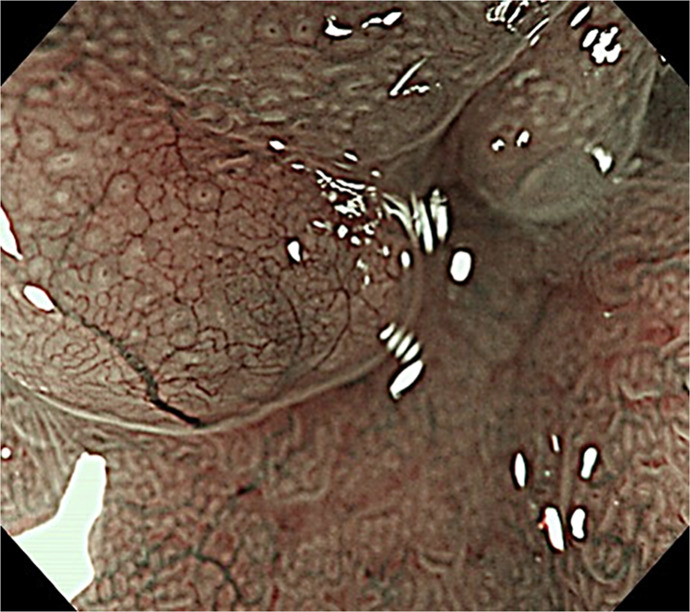

Case presentation: A female patient in her 60s had been taking PPI for reflux esophagitis for >10 years. An upper gastrointestinal endoscopy revealed two gastric polyps measuring 20 mm and 10 mm. She was referred to our hospital for resection, but narrow-band imaging revealed a nonneoplastic lesion. PPI was discontinued, and step-down therapy using vonoprazan was performed. During the treatment, a lifestyle guidance app (Muneyake PRO) was used to record daily heartburn symptoms, oral medication status, and daily life status. She was worried that her symptoms would worsen due to discontinuation, but she gained her understanding when the use of the app to monitor her symptoms was explained. The app was useful for understanding the progress of symptoms and the status of oral medication. Step-down therapy was performed only twice after PPI discontinuation, symptoms have not worsened, and follow-up endoscopy revealed significant gastric polyp shrinkage.